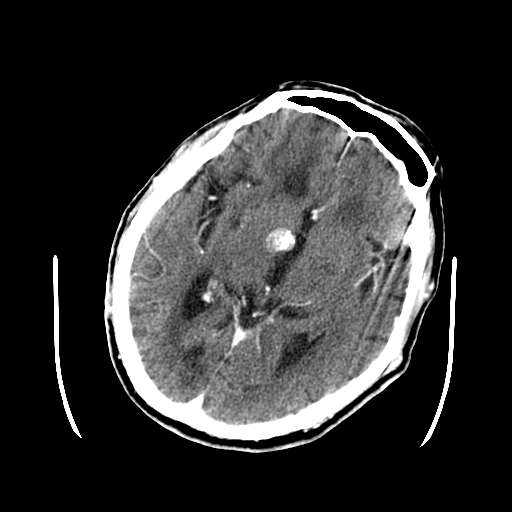

皮脑应该可以诊断,不知道增强病灶有没有强化(ct值),从片上看好像有轻度强化,定位像是脑外的,圆形高密度,内部有点状更高密度考虑为点状钙化,首先考虑为脑膜瘤.鉴别诊断:胶质瘤,垂体瘤,听神经瘤等.

这次病变主要是是因为脑干及小脑的梗塞,另外原有多发脑梗塞。右侧鞍上池及颞叶区可见一大部钙化的病灶,强化后略有增大,并见一条血管进入,考虑血管瘤。不排除脑膜瘤可能!~!

无占位,无水肿带,大部分钙化,av畸形?增强的图片都不尽量在同层面,难比较强化,如果有强化迹象肯定是av畸形!

无占位,无水肿带,大部分钙化,av畸形?或钙化灶?多发腔梗

考虑血管瘤。不排除脑膜瘤及单纯钙化可能!